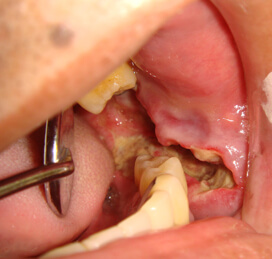

頬粘膜がん